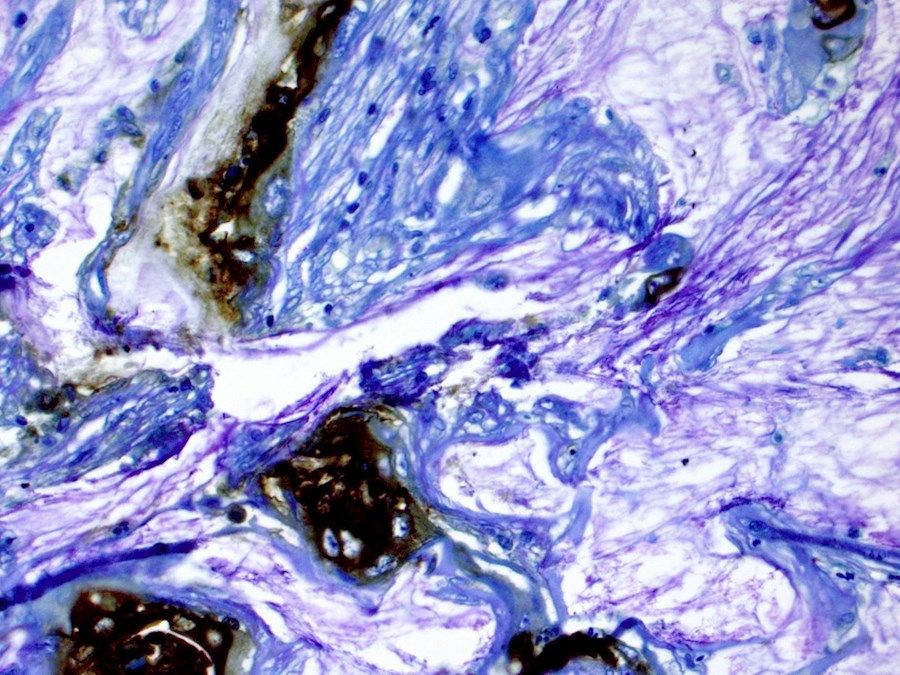

El bajo nivel de oxígeno, llamado hipoxia, es una característica conocida del microambiente del cáncer de páncreas y contribuye a la agresividad del tumor y la resistencia a la terapia. Sin embargo, el impacto de los altos niveles de CO2 en el cáncer de páncreas ha sido considerablemente menos estudiado.

Investigaciones anteriores habían demostrado que el microambiente del tumor pancreático alberga niveles aumentados de CO2. Aquí, el equipo demostró que aumentar el CO2 en cultivos celulares a los niveles observados en pacientes pulmonares era suficiente para aumentar su crecimiento y agresividad.

Cuando estas células con alto contenido de CO2 fueron tratadas con agentes quimioterapéuticos comunes y radioterapia, mostraron una mayor resistencia en comparación con las células cultivadas en condiciones normales de CO2 .